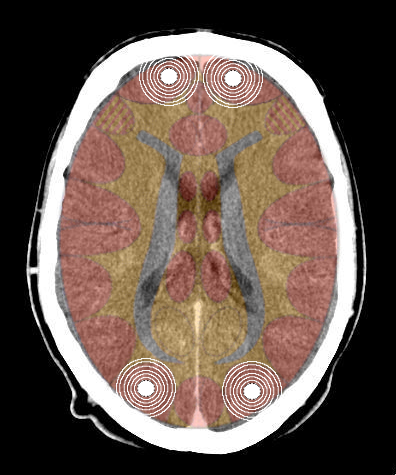

5.3.4.1 Uomini e donne destrimani

- Quando la persona è già maniacale, il terzo SBS impatta l'emisfero sinistro e getta la persona in una maniacalità più intensa

- Quando la persona è già in depressione, il terzo SBS impatta l'emisfero destro getta la persona in una depressione maggiore.